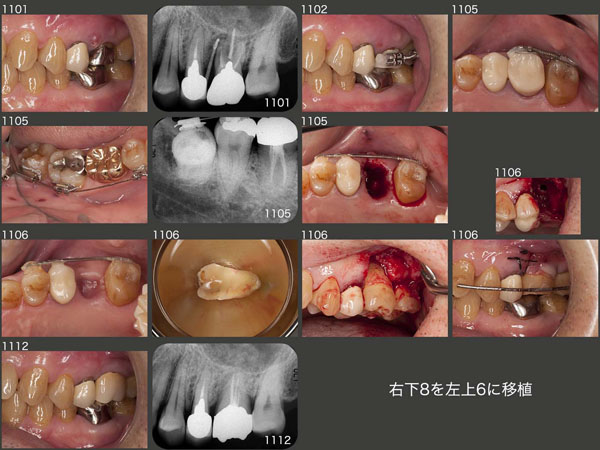

2011年1月,左上6にフィステルが生じた.この原因は近心頰側根の根尖病巣が考えられるが,口蓋根に9mmの歯周ポケットが出現したことから,同根に歯根破折が生じている可能性が高いと診断した.そこで,右下8をドナー歯として左上6部に移植する計画を立てた.なお,右下8の歯根のサイズのほうが左上6のそれより大きかったので,抜歯予定の左上6を固定源にして,左上7を遠心に少し移動させた.11年5月に抜歯し,6月に移植を行った.なお,右下8を抜歯しやすいように,事前に挺出力を加えておいた.また抜歯時,左上6は上顎洞の穿孔が認められた.

移植に際しては,ドナー歯を90°回転し何とか抜歯窩に収めたが,頰側には歯槽骨が存在しなかった.この時は,歯根と歯肉弁との間に補塡材は用いず,血餅のみのまま縫合した.移植後,9月の時点で歯周ポケットは3mm以下となり,12月に硬質レジン前装冠を装着した.頰側の歯槽骨は歯根の半分ぐらいしか回復していないが,歯槽骨の上に結合組織性の付着が得られていれば,幸いである.